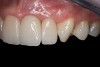

Fig 24. Final restorations 7 months after cementation of the crowns.

Figure 24

Fig 25. Final restorations 7 months after cementation of the crowns.

Figure 25

Fig 26. Final restorations 7 months after cementation of the crowns.

Figure 26

The 4 crowns, with the resin cement, were placed onto the preparations and cemented using the “tack and wave” technique as described by this author in a previous publication18 (Figure 20). Each crown was “tacked” into place using a 2-mm light guide for 1 second on the facial and 1 second on the lingual, away from the margins (Figure 21). An 8-mm light guide was then placed on the curing light, and each crown was “waved” from approximately 1 inch from the surface for 2 seconds from the buccal and lingual aspects (Figure 22). After the “waving” of the margins, excess partially polymerized resin cement was easily removed using a #12 Bard Parker Blade (Figure 23). Waxed dental floss was then used interproximally to remove any excess cement at the interproximal gingival margins. A glycerin-based oxygen-inhibition gel was then placed around all margins. The crowns were light-polymerized for 40 seconds per tooth using a multi-wavelength LED curing light. After complete polymerization, the oxygen-inhibition gel was rinsed away and any excess cement was removed using a scalpel blade or scaler. Occlusion was evaluated and adjusted, and the restorations and any adjusted porcelain were polished using a porcelain polishing system. Figure 24 through Figure 27 show the final outcome 7 months after cementation of the crowns.